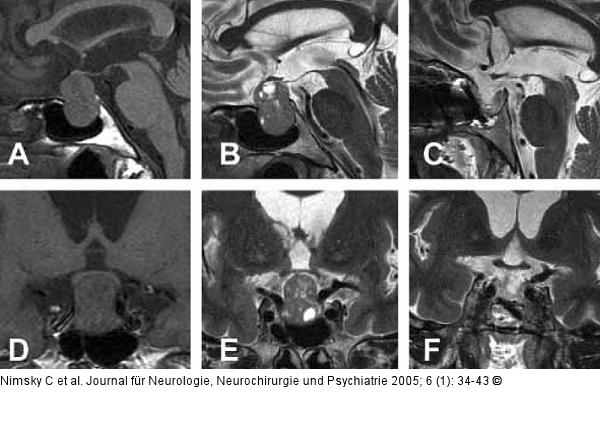

Abbildung 3: Hypophysenadenom Intra- und suprasellär entwickeltes, hormoninaktives Hypophysenadenom bei einer 72jährigen Patientin, die durch eine sekundäre Nebennierenrindeninsuffizienz aufgefallen ist. A/D: präoperative T1-gewichtete Bildgebung, B/E: präoperative T2-gewichtete Bildgebung mit einer erhöhten Detailgenauigkeit; C/F: die entsprechende intraoperative T2-gewichtete Bildgebung bestätigt die komplette Exstirpation. |

Abbildung 3: Hypophysenadenom

Intra- und suprasellär entwickeltes, hormoninaktives Hypophysenadenom bei einer 72jährigen Patientin, die durch eine sekundäre Nebennierenrindeninsuffizienz aufgefallen ist. A/D: präoperative T1-gewichtete Bildgebung, B/E: präoperative T2-gewichtete Bildgebung mit einer erhöhten Detailgenauigkeit; C/F: die entsprechende intraoperative T2-gewichtete Bildgebung bestätigt die komplette Exstirpation. |